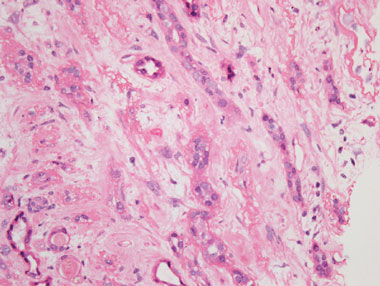

A renal ultrasound revealed unobstructed, small kidneys with cortical thinning bilaterally. A renal biopsy showed severe tubulointerstitial fibrosis and atrophy. There was no evidence of glomerulonephritis, nor of acute tubular necrosis (Box). These findings were consistent with chronic exposure to a nephrotoxin.

Some herbal products contain aristolochic acid (AA), which is known to be nephrotoxic and carcinogenic.3 Aristolochic acid nephropathy (AAN), first reported in Belgium as “Chinese herbal nephropathy”,4 is characterised by progressive fibrosing interstitial nephritis leading to renal failure and severe anaemia. AAN is a worldwide problem, but its true incidence is unknown and probably underestimated,5 and though many cases of AAN have been reported, to our knowledge this is the first reported case in Australia. Many countries have prohibited the production and sale of herbal products containing AA,6 but despite bans, these products continue to be available through the internet or supplied through mail order.